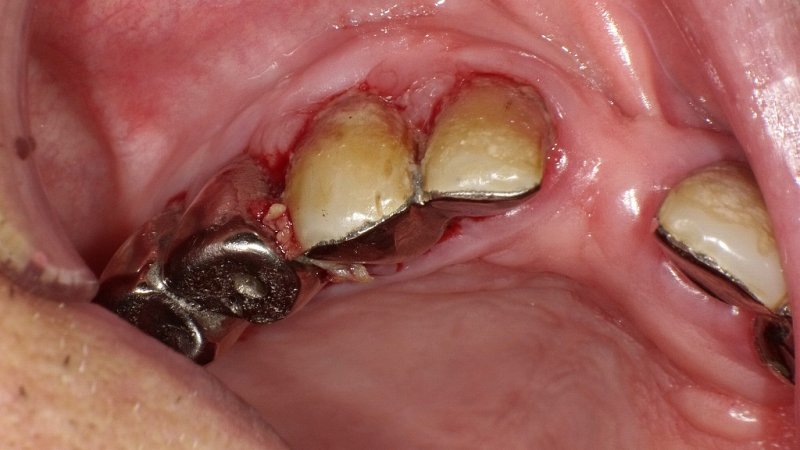

当院は、歯周病および重度歯周病の治療に特化した専門的な歯科医院です。最新の歯槽骨再生療法をはじめ、歯周外科・フラップ手術や3DS除菌療法など、多岐にわたる治療法をご提供しています。

熟練した歯科衛生士によるメインテナンスや歯石除去により、日常的なケアも万全です。さらに、歯周内科治療や遺伝子診断を取り入れ、個々の患者様に最適な治療プランを提供します。